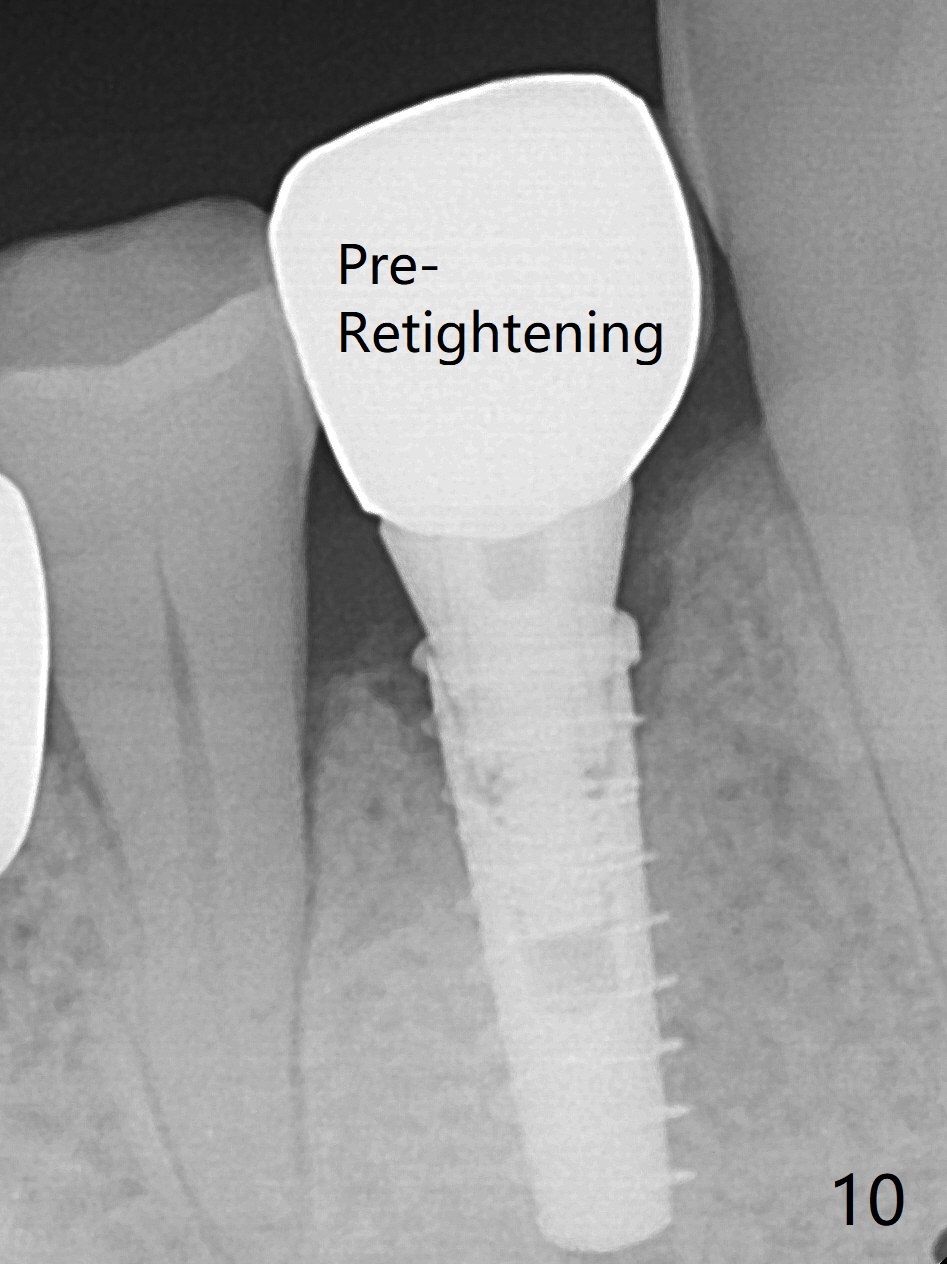

In fact the mesiodistal space of the site of #28 is within normal limit. The buccal plate atrophy is striking (Fig.1) with a fistula (^, associated with underlying residual root tip). When the flaps are raised, the ridge is triangular with the lingual plate (Fig.2 *) higher than the buccal one. Because of the slope, the multiple-drill approach is adopted in stead of single-drill one, because the marking bur is wobbling after 1.6 mm osteotomy at 13 mm (Fig.3). After placement of a 4x11 mm implant, a 4.5x4(2) mm abutment is inserted (Fig.4). The abutment and the implant act as a mesh (framework) so that bone graft and collagen membrane can be laid upon them buccolingually. When the flaps are sutured, there is less tension than that without the abutment. Furthermore, the buccal tissue volume seems to be increased (Fig.5 (<: fistula, which should heal soon), as compared to Fig.1). Tale photos to show effectiveness of the simultaneous GBR and disappearance of the fistula. Three months postop (Fig.6,7 (incomplete abutment seating)), the implant is loaded for intrusion of the opposing supraerupted tooth. The patient returns with chief complaint of food impaction between #27 and 28 three years 7 months post cementation; there is an open contact. Before pick up impression the distal convex surface of #27 is trimmed. The repaired crown has tight proximal contacts before (Fig.9,10) and after (Fig.11) retightening and cementation.